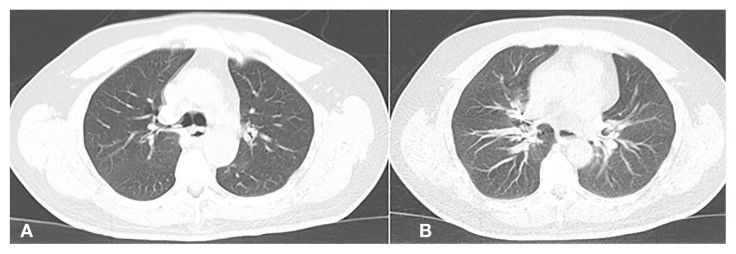

Пациент утверждал, что не помнит об аспирации. КТ органов грудной клетки подтвердила наличие инородных тел в бронхиальном дереве справа (рис. 2 — А, В) и возможный превертебральный абсцесс, который объяснял дисфагию пациента.

Рисунок 2 [1].